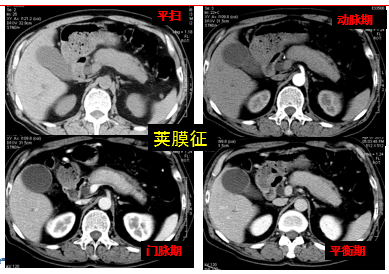

胰腺周围出现增厚的包膜样结构,呈 「 鞘膜 」 征或 「 荚膜 」 征。CT 平扫呈等或稍低密度,动脉期强化较弱,呈明显的延迟强化。与胰腺纤维组织的高度增生有关。

弥漫性

男,58 岁,腹痛黄疸、胆肠引流术后四年,反复黑便十天